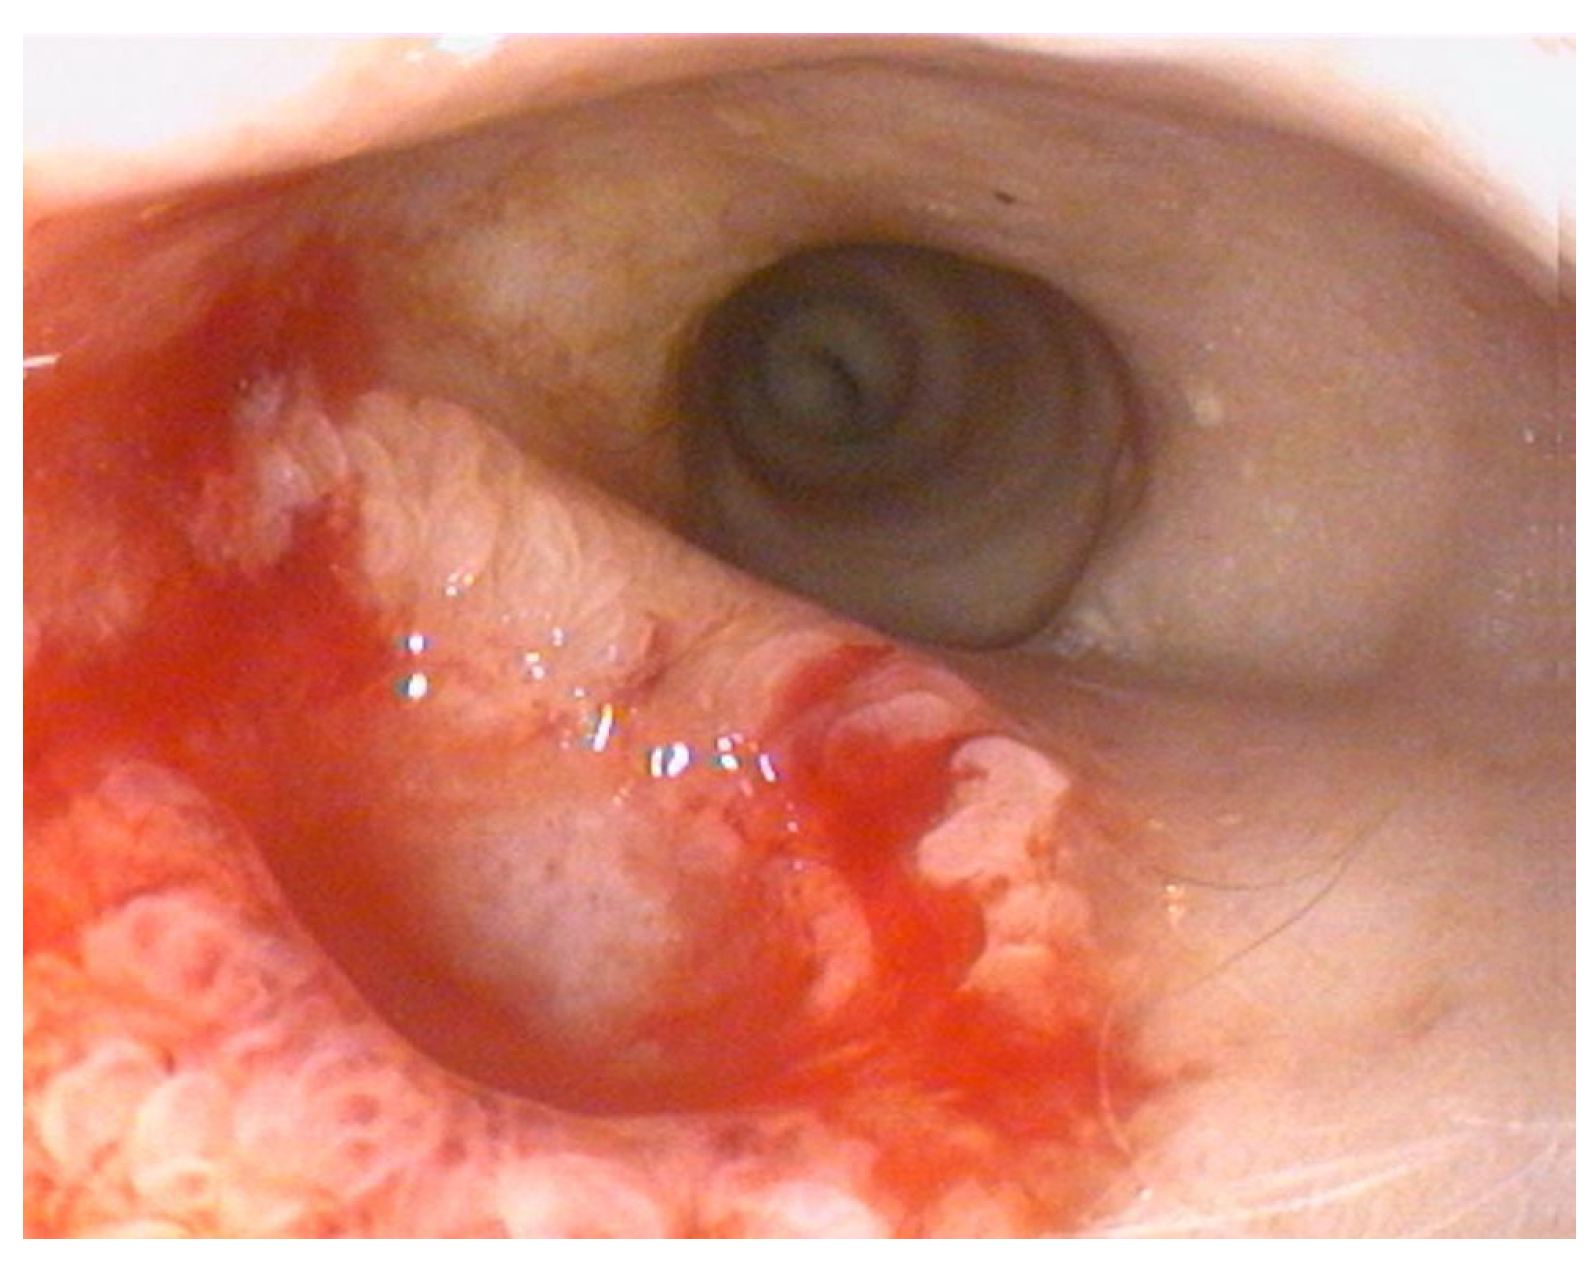

Histopathological examination of the gastric biopsies revealed mucosa with deep, hyperplastic crypts and occasional erosive and ulcerated areas replaced by necrotic and collagenous material containing abundant eosinophils, together with a mixed inflammatory infiltrate of neutrophils, small lymphocytes, and scattered eosinophils. Duodenal biopsies, including those obtained distal to the mass, showed irregular, shortened and fused villi with a moderate mixed lymphoplasmacytic infiltrate containing neutrophils and eosinophils in the lamina propria. Histopathological examination of the duodenal mass revealed a sample devoid of recognizable microanatomical architecture, composed of fibrocollagenous tissue interspersed with densely cellular areas (Figure 2). Overall, the findings were consistent with eosinophilic and fibroplastic gastroenteritis compatible with feline gastrointestinal eosinophilic sclerosing fibroplasia (FGESF).

Figure 2. Histological section of endoscopic duodenal biopsy showing dense eosinophilic infiltrates and marked fibroplasia with disrupted mucosal architecture H&E, 200×, scale bar = 200 µm.